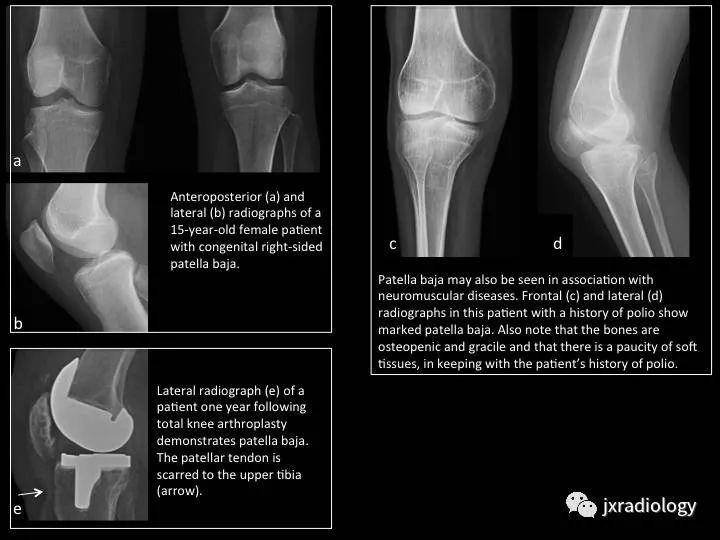

Fig. 8: Patella baja

图8:低位髌骨

a,b图,15岁女孩右膝先天性低位髌骨。

c,d图,低位髌骨也见于神经肌肉疾病;患者既往有脊髓灰质炎病史。

e图,人工膝关节置换后患者一年复查,侧位片提示低位髌骨;箭头是髌韧带疤痕形成。